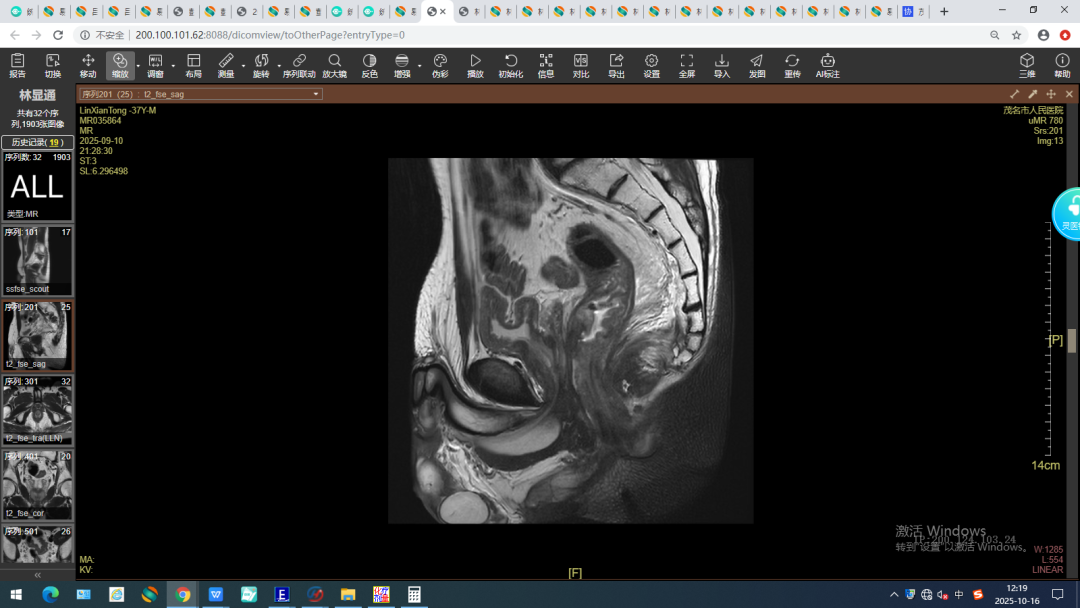

(治疗后)

经过为期一个多月的新辅助同步放化疗,复查结果显示,林先生的肿瘤体积已明显缩小,手术条件成熟。9月中旬,胃肠外科团队为林先生成功实施了腹腔镜直肠癌根治术。术后病理报告证实,新辅助治疗效果显著,肿瘤已明显消退,淋巴结也未发现转移,患者目前已顺利恢复出院。